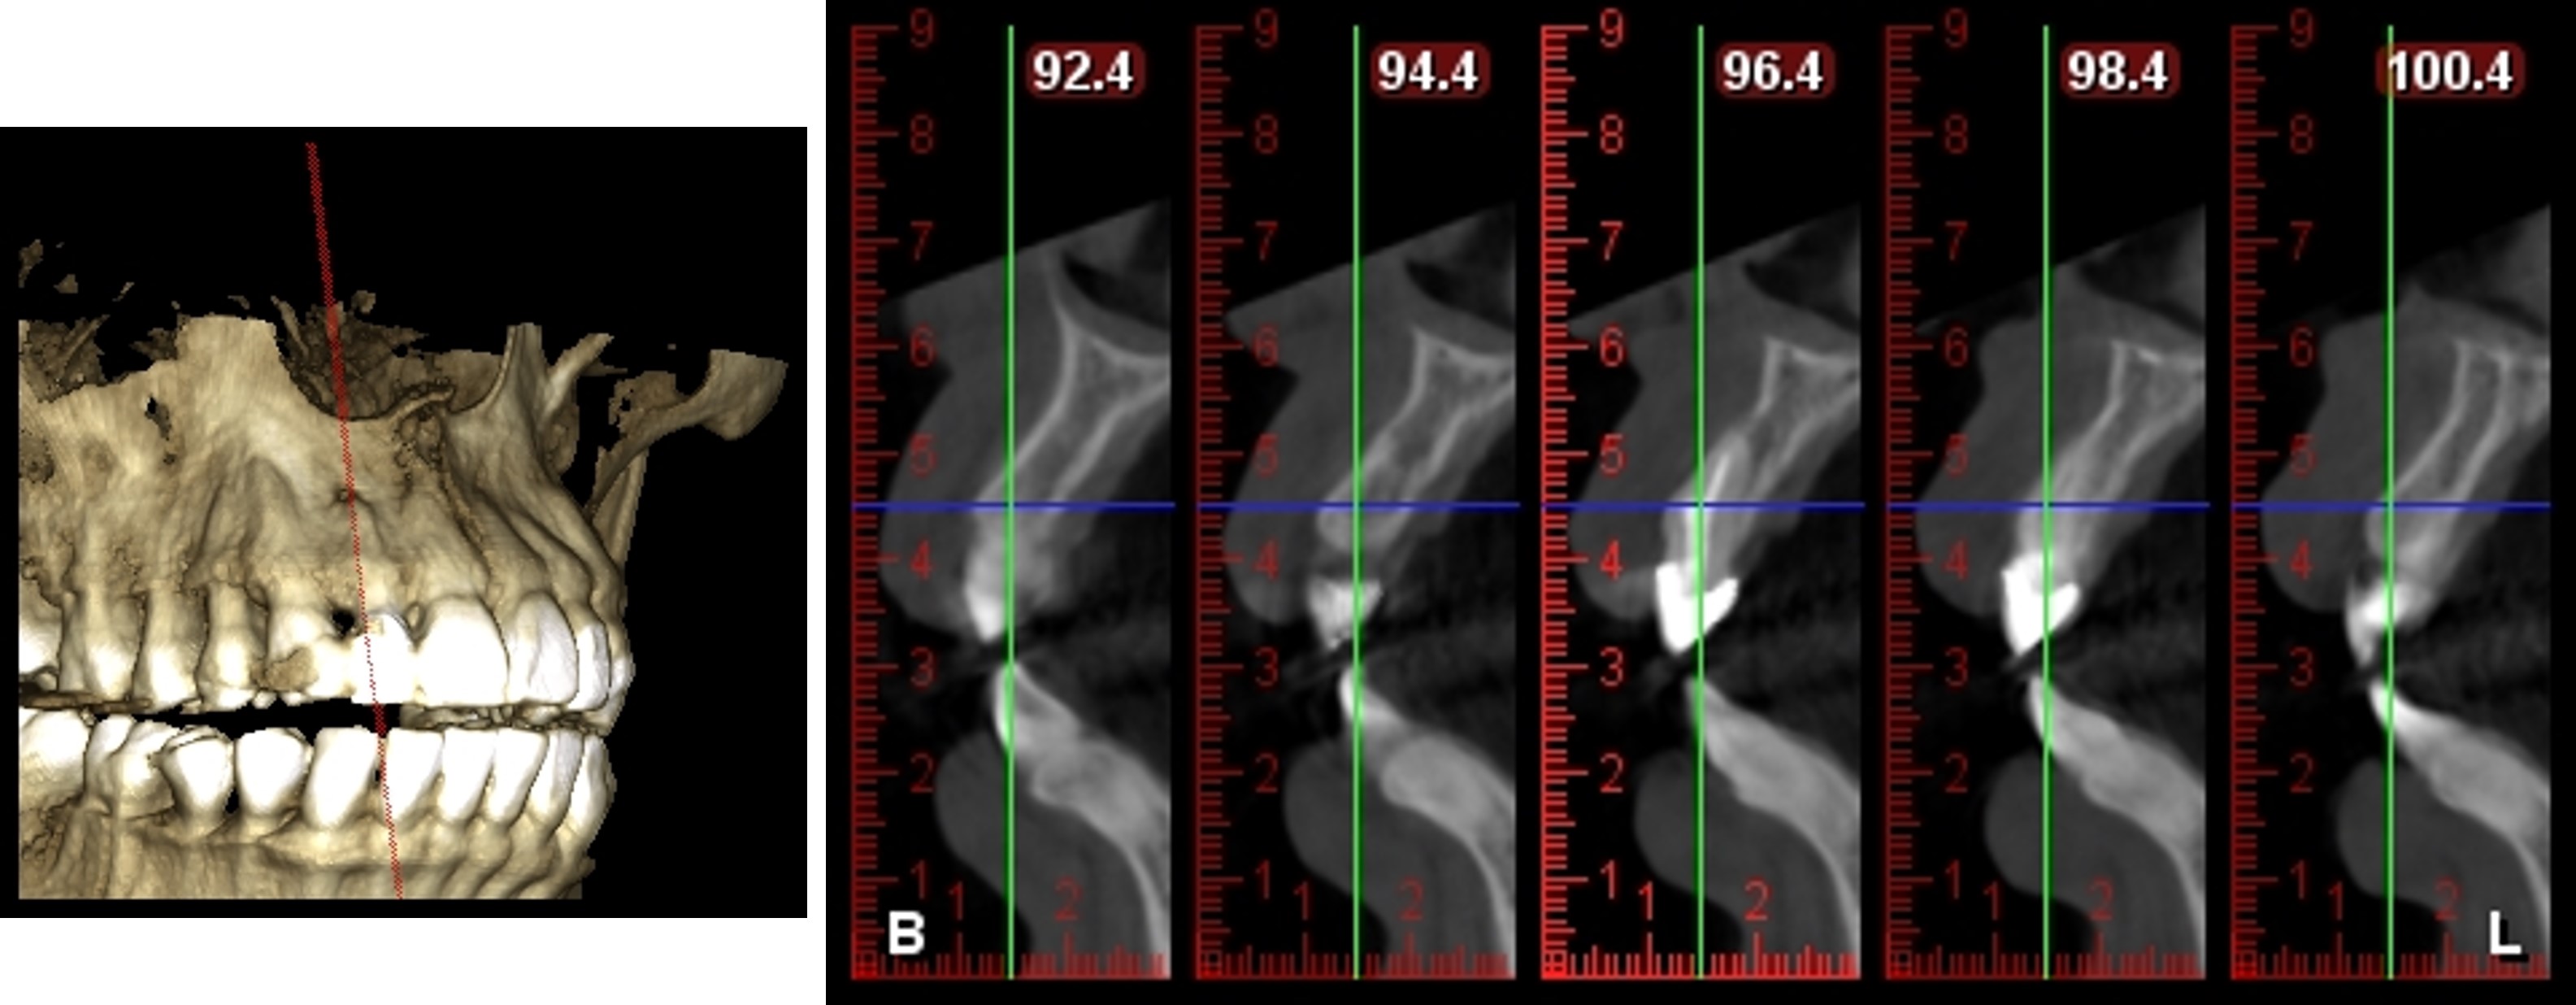

手術前CT評估